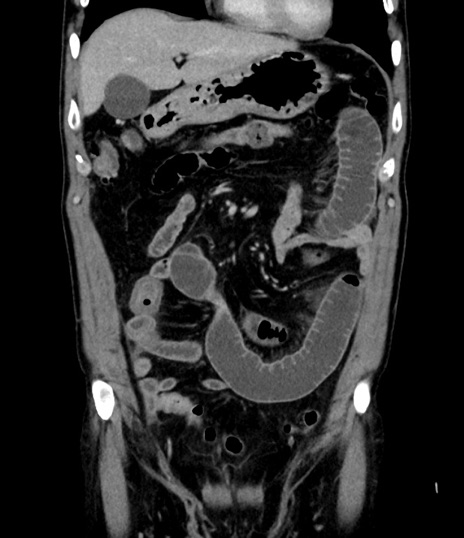

症例8(冠状断像)

【症例】 60歳代男性

【主訴】 黒色吐物

【現病歴】 4日前から嘔気自覚、2日前の朝食後にも嘔気あり、自分で手で嘔吐反射起こし嘔吐したところ血が混ざっていたため受診。

【既往歴】 5年前汎発性腹膜炎を伴う急性虫垂炎で手術、高血圧、前立腺肥大症、高脂血症

【身体所見】 腹部正中に手術癩痕あり 腹部平坦・軟圧痛なし膨満感あり

【データ】WBC 8400、CRP 4.54